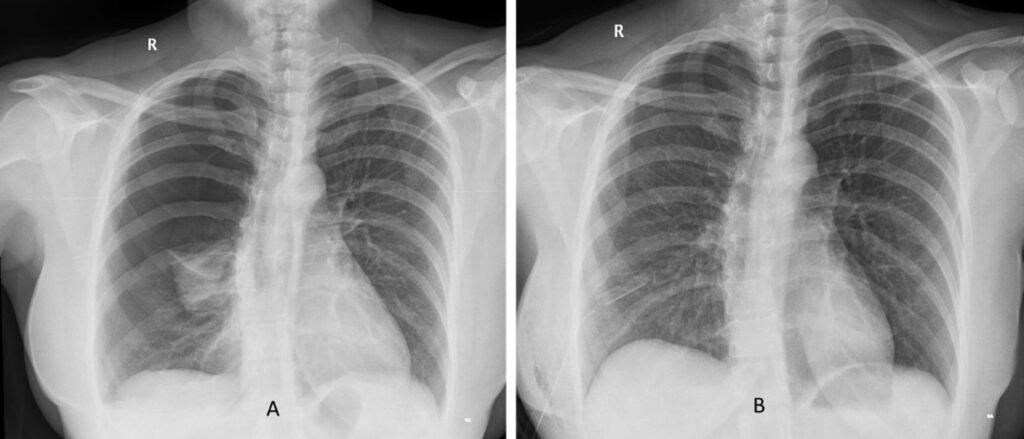

- Katamenial pneumothorax: I sjældne og alvorlige tilfælde kan tilstanden føre til, at en lunge kollapser i forbindelse med menstruationscyklussen. Dette er en livstruende tilstand, der kræver øjeblikkelig lægehjælp.